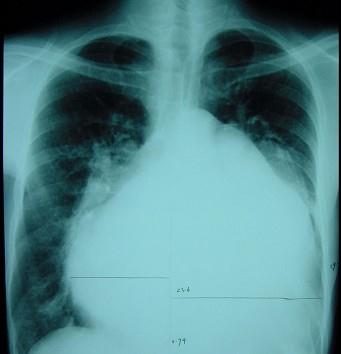

此心脏正位片描述正确的是 ( )A、“普大型”心脏B、“二尖瓣型”心脏C、“中间型”心脏D、“横位型”心脏E、“主动脉瓣型”心脏

问题 此心脏正位片描述正确的是 ( )

选项 A、“普大型”心脏 B、“二尖瓣型”心脏 C、“中间型”心脏 D、“横位型”心脏 E、“主动脉瓣型”心脏

答案 A